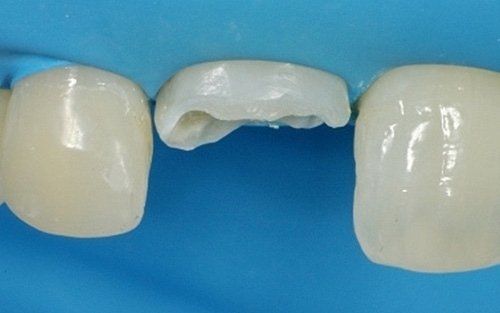

Qui raffigurato l'incisivo laterale di destra, dopo la rimozione del vecchio restauro.

Il restauro definitivo sul dente laterale: notare la buona integrazione fra il dente e il restauro.